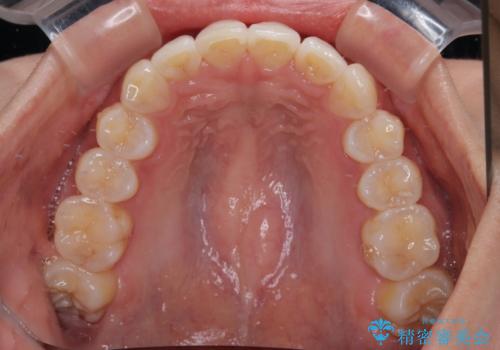

前歯のデコボコを治したい インビザライン矯正

- 上下前歯の叢生を気にして来院された患者様です。

インビザラインでの治療を希望されていて、デコボコの程度が中等度であり、安価なパッケージにて対応可能と判断されたため、インビザライン・モデレートを用いて矯正治療を行うこととしました。